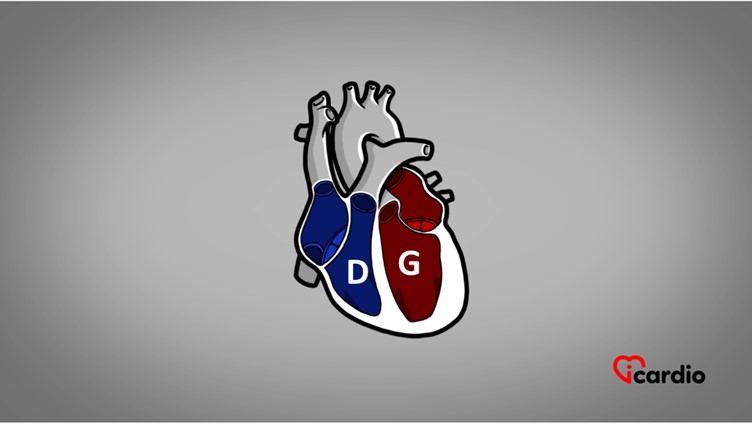

Les 4 cavités cardiaques

Le cœur est formé de 4 parties appelées cavités. Les 2 cavités supérieures, les oreillettesLes oreillettes sont les deux cavités supérieures du cœur. Elles agissent comme des réservoirs du sang qui ira remplir les ventricules. >>, sont les réservoirs du sangLe sang est composé de globules rouges, de globules blancs, de plaquettes et de plasma. Les globules rouges sont responsables du transport de l’oxygène et du dioxyde de carbone. Les globules blancs constituent notre système de défense >> qui ira remplir les ventriculesLes ventricules sont les 2 cavités inférieures du cœur. Ils sont plus musclés que les oreillettes; ils servent à propulser le sang pour assurer la circulation dans tout le corps. >>.

Les ventriculesLes ventricules sont les 2 cavités inférieures du cœur. Ils sont plus musclés que les oreillettes; ils servent à propulser le sang pour assurer la circulation dans tout le corps. >> sont les 2 cavités inférieures du cœur. Ils sont plus musclés que les oreillettesLes oreillettes sont les deux cavités supérieures du cœur. Elles agissent comme des réservoirs du sang qui ira remplir les ventricules. >>; ils servent à propulser le sangLe sang est composé de globules rouges, de globules blancs, de plaquettes et de plasma. Les globules rouges sont responsables du transport de l’oxygène et du dioxyde de carbone. Les globules blancs constituent notre système de défense >> pour assurer la circulation dans tout le corps.